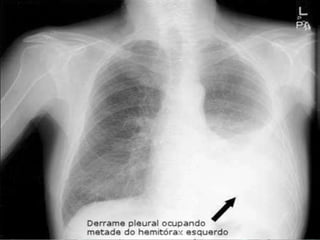

Derrame Pleural

• Hipotransparência;

• Denso e homogêneo;

• Em PA quando possuir

mais de 300ml;

• Em Laurell em

quantidades <300ml;

• Desvio do mediastino

para o lado oposto;

• Velamento do seio

costofrênico.

Derrame Pleural • Hipotransparência; •Denso e homogêneo; • Em PA quando possuir mais de 300ml; • Em Laurell em quantidades <300ml; • Desvio do mediastino para o lado oposto; • Velamento do seio costofrênico.